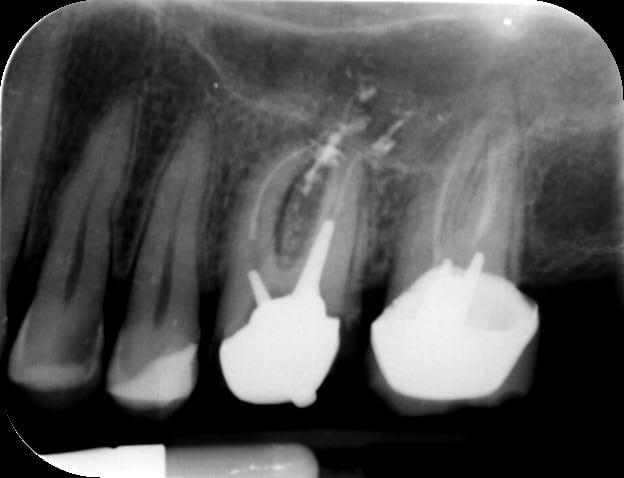

J'ai conclu par moi même qu'il fait de la merde en sur-équipant les patients , et récemment il fait de l'implanto . Voilà un superbe Not All on One , c'est un Ten On One . C'est beaaaaaauuu...)))

Img 3487 cuuqbi - Eugenol

Img 3488 h8ilol - Eugenol

Img 3489 cuhdog - Eugenol

Img 3491 pjrhic - Eugenol

Précision : Un correspondant et ami s'est chargé de l'extrimplantraction...car faut toujours avoir Dieu derrière soi pour combattre le diable devant les tribunaux . "Bin quoi ? Il était farpètement intégré mon implant , et dans le bon axe en plus !"